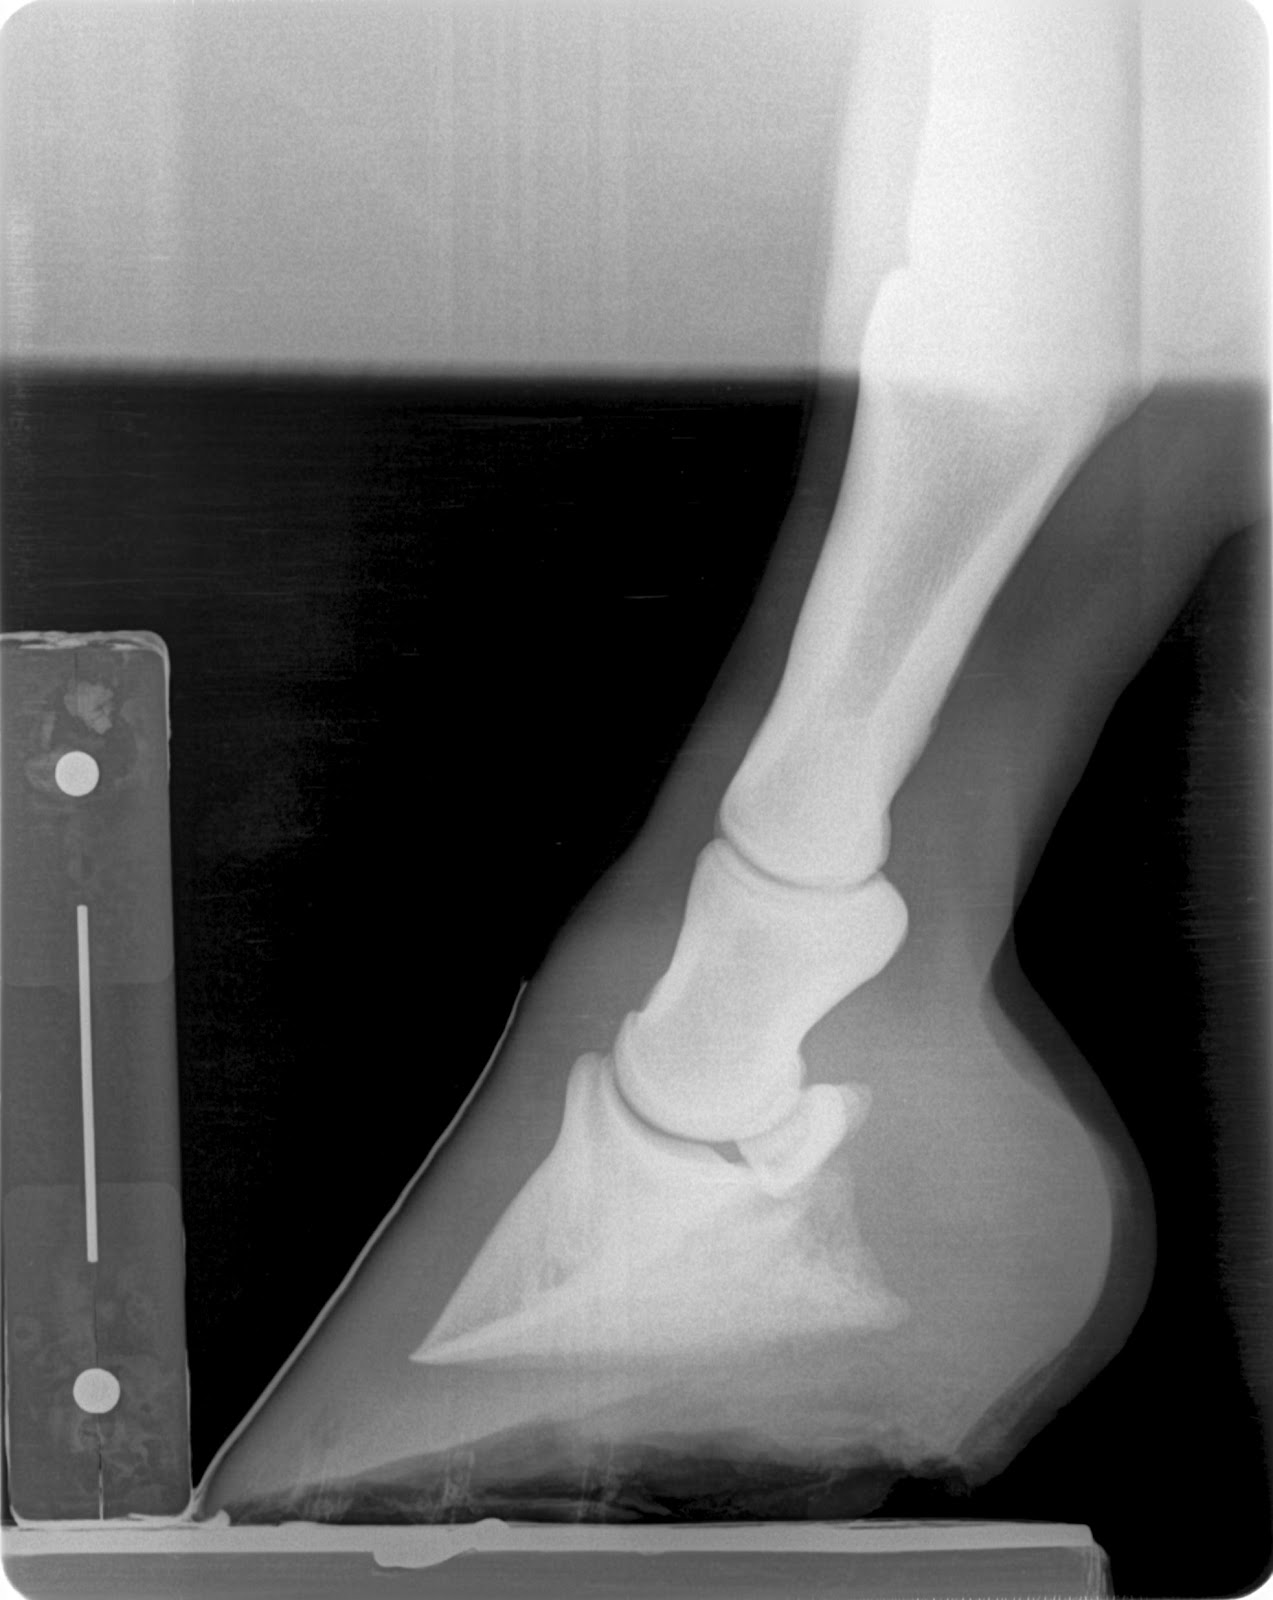

Below are images of the navicular bone, pre and post shoe podiatry radiographs and digital photos of the patient.

1/5 lame bilateral but 2/5 on left turn in a tight circle. Left front is a grade 1+ club and podiatry style films confirm healthy soft tissue parameters. My thought process is: With healthy sole depth and minimal remodelling of the apex of coffin bone on a club foot I want to next look at the navicular bone to evaluate for lesions. This case shows significant lesions in several views. This are most likely in the distal half of the flexor cortex of the navicular bone. I find these similar lesions in younger non lame patients but I do feel as they reach middle age they begin to create lameness. Dr. Redden feels that the navicular bone of the club foot does not recieve as much load from the tendon versus the lower profile foot and does not develop as strongly as the low foot. I am beginning to feel that these lesions are developmental and become more degenerative with age and use. If dissected out these lesions will be a slight depression in the flexor cortex with a roughened edge that likely causes some abrasiveness to the deep digital flexor tendon.

Note the better digital alignment the drastic change in palmar angle, tendon surface angle and reduced toe lever. This shoe changed PA by 12-14 degrees which will unload the tendons load on the navicular bone by 50 to 60 percent.